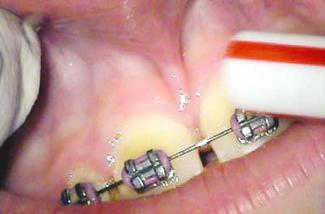

After infiltration of 1cc of local anesthetic solution, the Er:YAG laser (OpusDuo, OpusDent USA) was used at 350mj with a 1,000-micron, contact sapphire tip and heavy water spray to gently ablate the frenal attachment and underlying muscle tissue down to the level of the periosteum (figures 2, 3, and 4). Once this is accomplished, there is a small defect in the vestibular mucosa and interdental papilla where the frenal attachment and muscle once was. There is no charring, no burned tissue, and free bleeding in the site (figure 5).